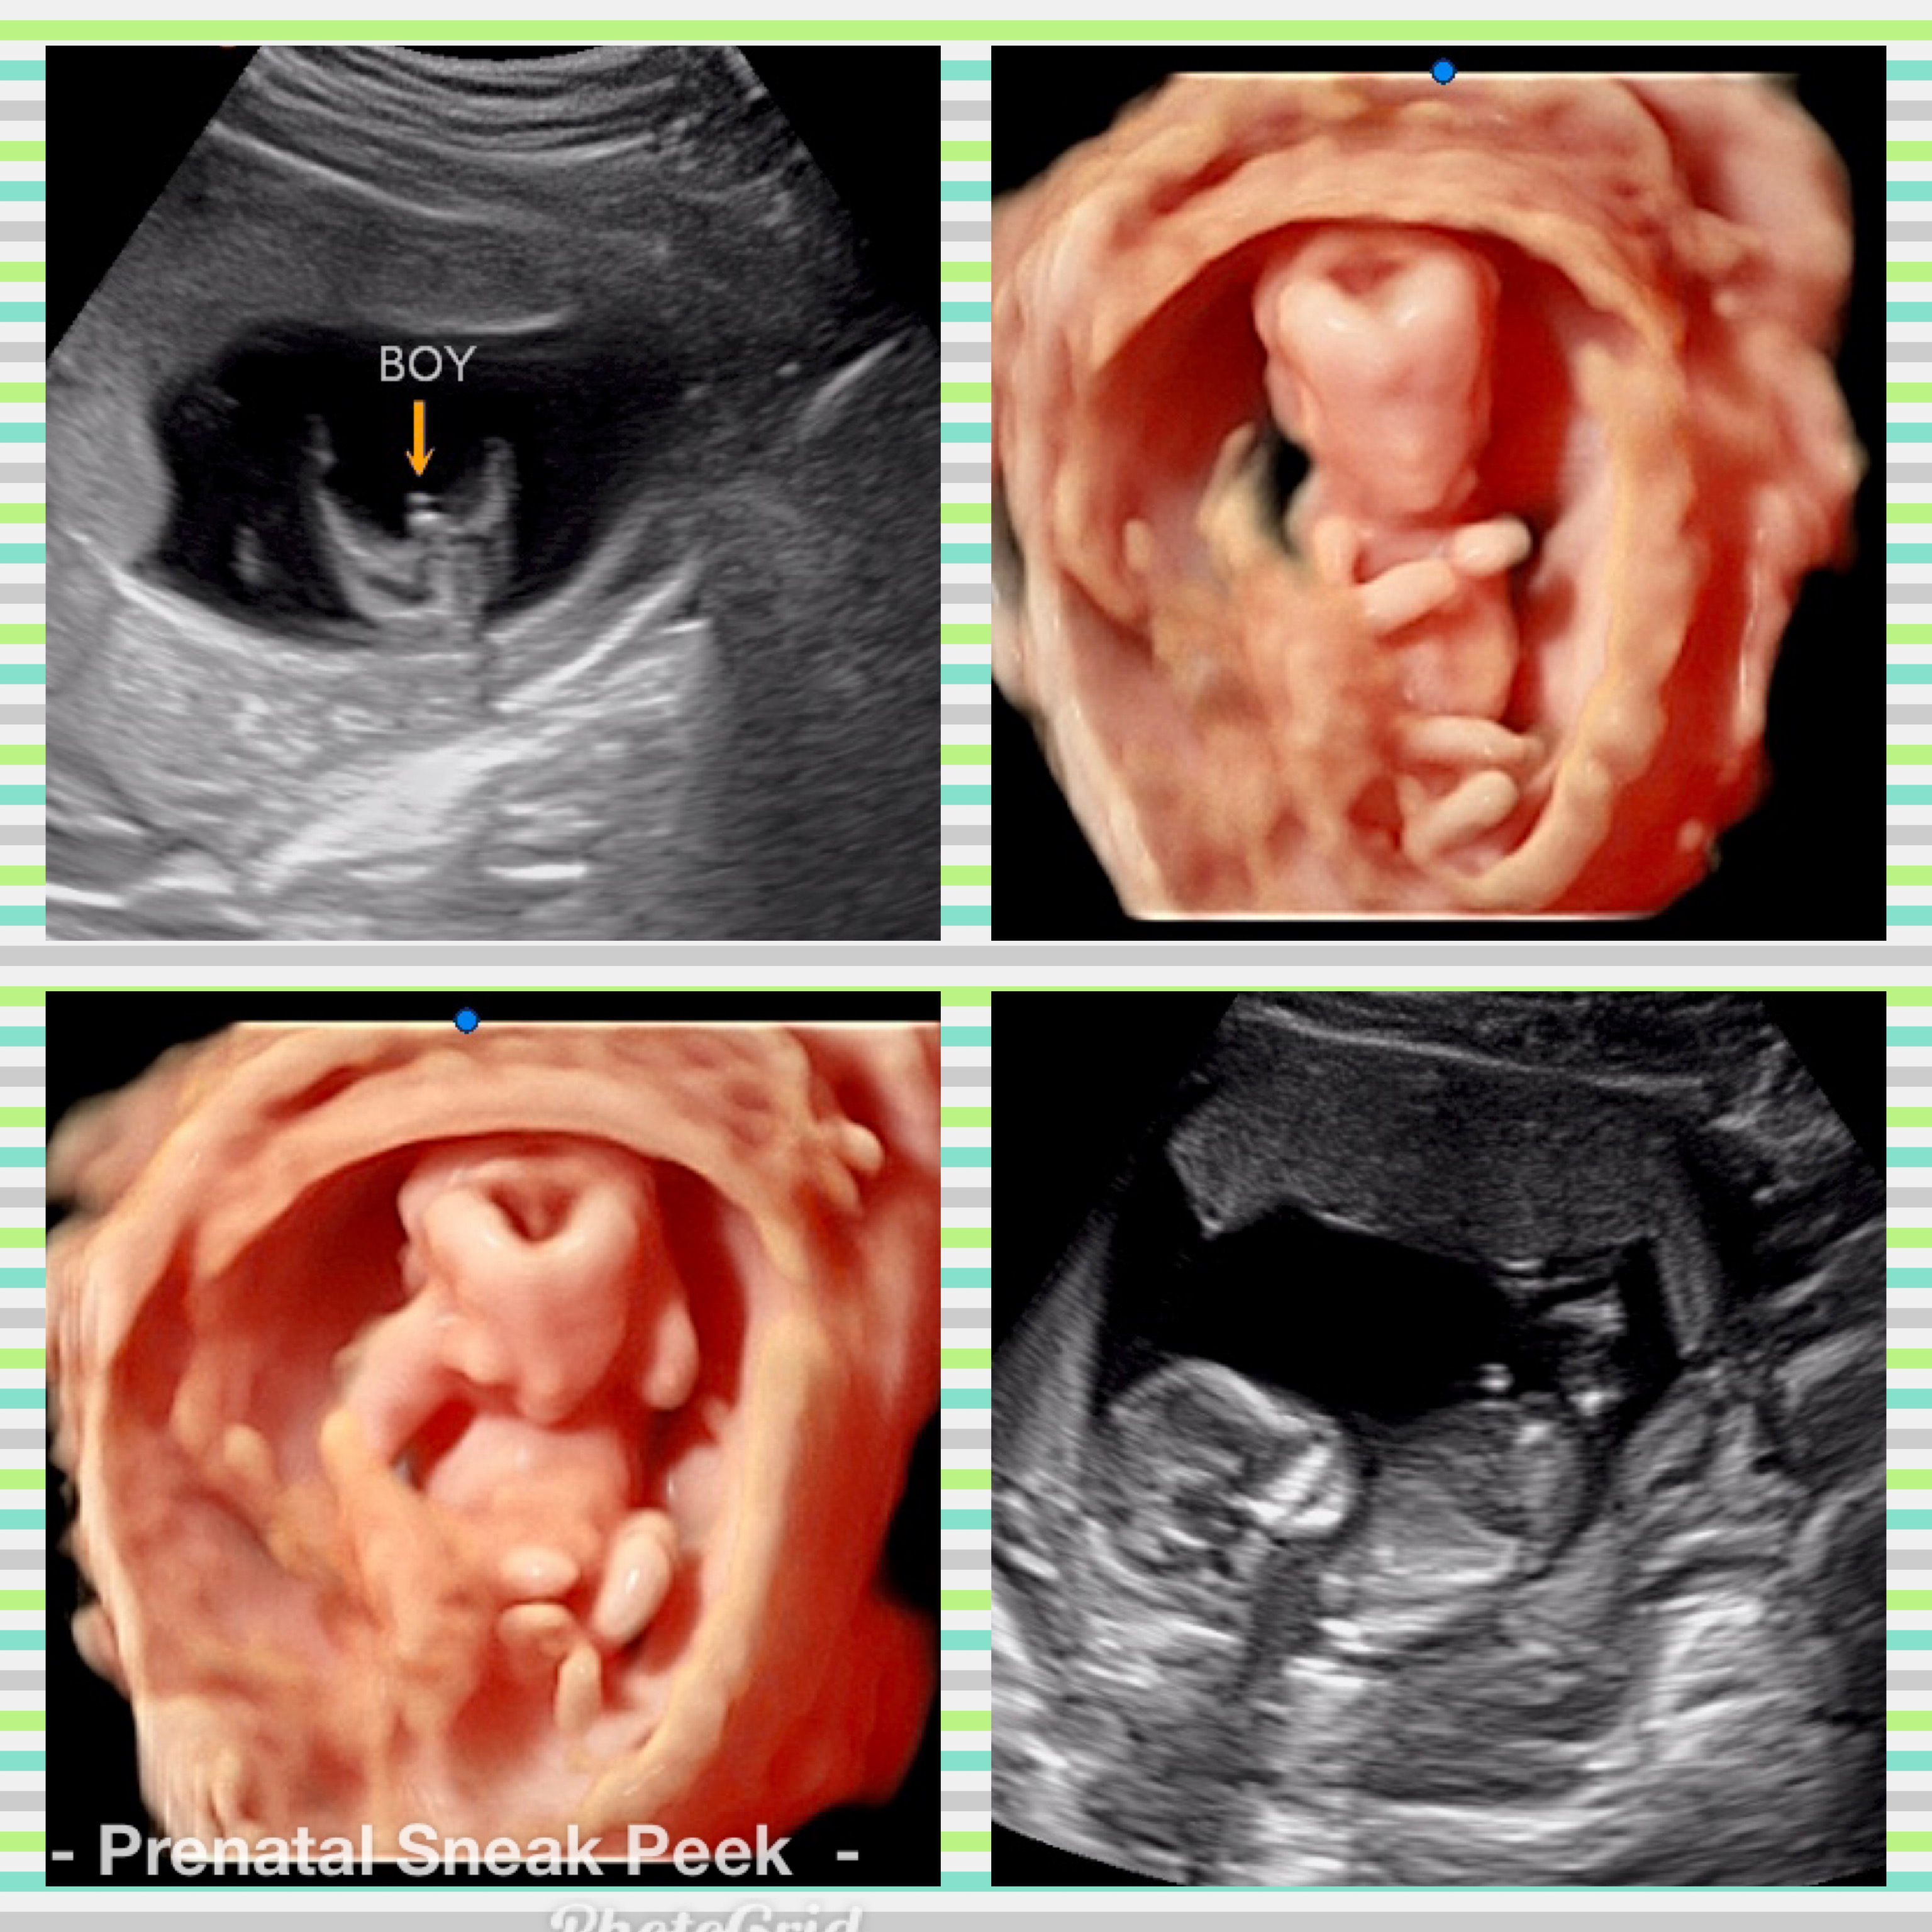

ABOUT PRENATAL SNEAK PEEK

Prenatal Sneak Peek is an elective mobile ultrasound company that provides ultrasounds in the comfort of your home. It is owned and operated out of Bel Air MD. Owner, Kelly Wargo, RDMS is a Registered Diagnostic Medical Sonographer with a specialty certification in OB. She has over 15 yrs. experience in the field of ultrasound. Kelly is the sole operator of her business; therefore, you will get the same quality every time! She also has a heart for saving babies, providing ultrasound services part-time to Options@328 a nonprofit located in Baltimore City.